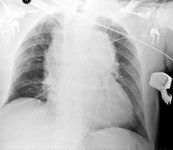

Chest x-ray showing a widened mediastinum

From the collection of Professor James Brown; used with permission